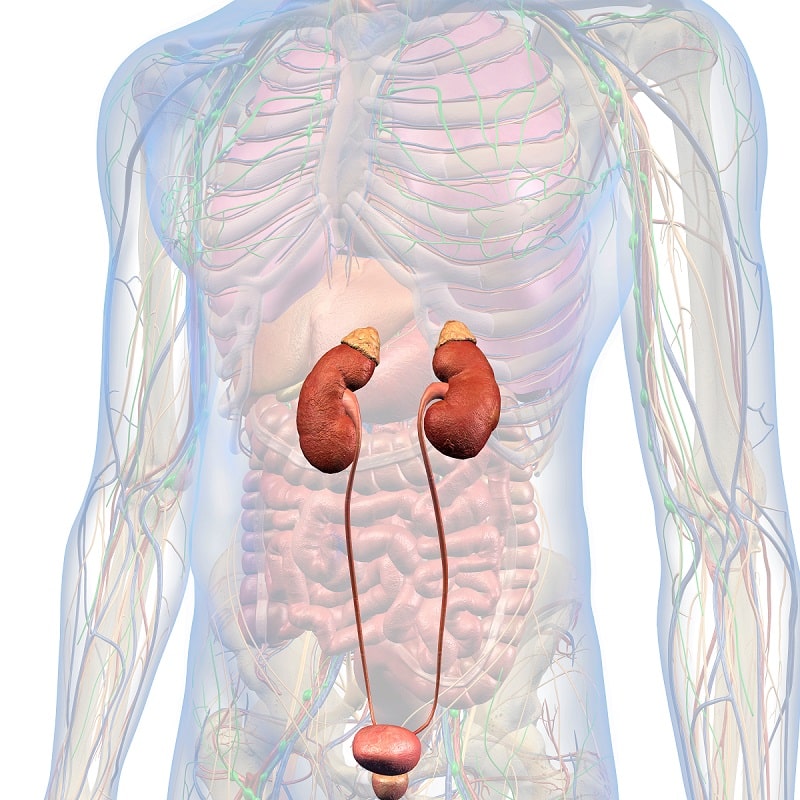

Anatomía humana

Es la ciencia que estudia las estructuras macroscópicas del cuerpo humano. Estudia las estructuras del cuerpo humano por sistemas, como son, el sistema esquelético, el nervioso, el vascular, etc.